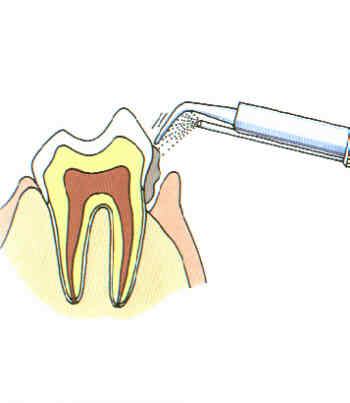

Ultraschall-Zahnsteinentfernung

Am schonendsten wird Zahnstein mit einem Ultraschallgerät entfernt. Eine Ruhigstellung ist dazu erforderlich.